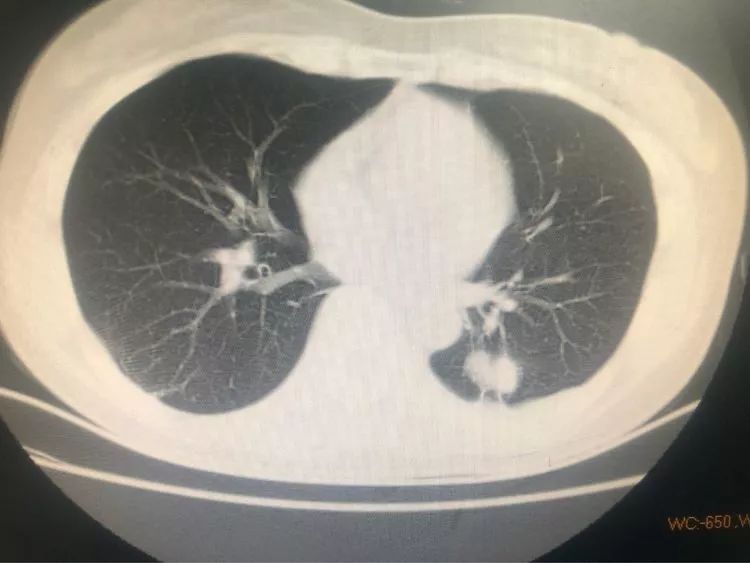

第三例 吳大伯今年55歲,右上肺后段結節(jié)樣病變,伴有鈣化,一般這種情況大家都會覺得是結核球。

由于患者門診抗結核治療病灶稍增大,醫(yī)生們經(jīng)商議最終決定穿刺。雖然從影像看起來沒有穿刺路徑,不過沒關系,省胸科醫(yī)院經(jīng)驗豐富的內(nèi)科醫(yī)生們可以通過體位來調整。

待病理報告出來后告訴我們,結核是存在的,同時見不典型增生。

注意了,見不典型增生,就是癌前病變,但目前還不是癌,此時正是最佳手術時機,是可以治愈的!如果再晚一些時間,也許就沒機會了!